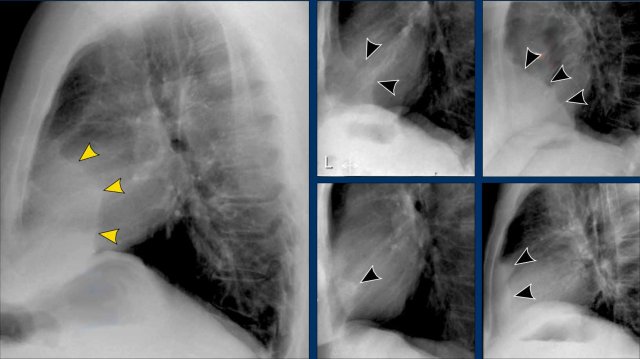

Displacement of the Azygoesophageal Line (1) – Hiatal hernia

A hiatal hernia (arrowheads) is the most common cause of displacement of the azygoesophageal line as seen on the PA-view.

Notice the air within the hernia on the lateral view (black arrow).

Displacement of the Azygoesophageal Line (2) – Subcarinal Lymphadenopathy

A common cause of displacement of the azygoesophageal line is subcarinal lymphadenopathy (station 7).

On the chest X-ray, note superior displacement of the azygoesophageal line just below the carina, consistent with enlarged subcarinal lymph nodes (black arrow).

Additional right paratracheal lymphadenopathy is seen, displacing the right paratracheal stripe (white arrow) and deviating the trachea to the left.